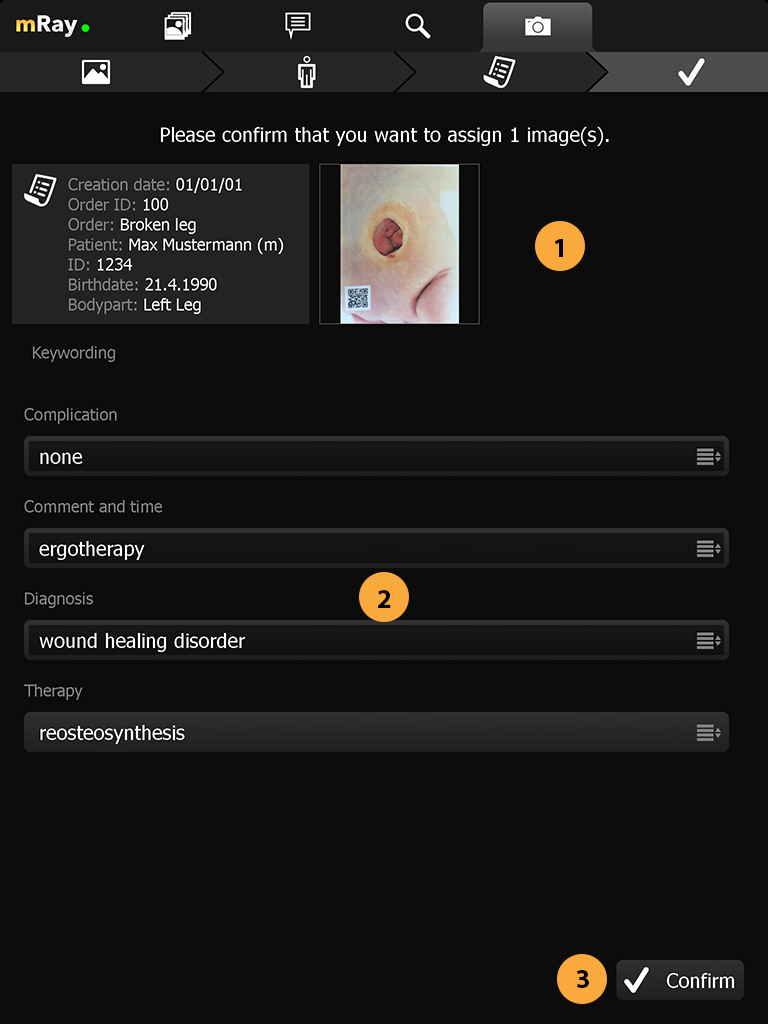

Aufnahme von Bildern zur Wunddokumentation. Versand der Aufnahme als DICOM Datei an ein PACS inkl. aller notwendigen Meta-Informationen